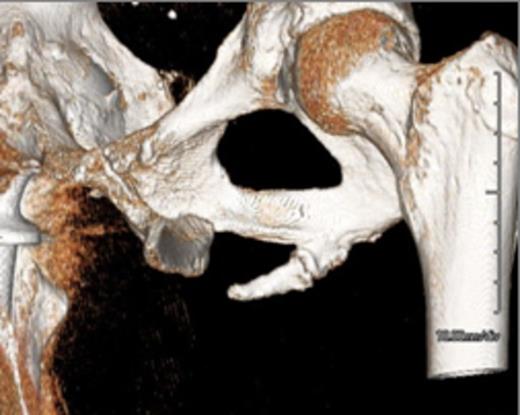

Representative images, including: a plain radiograph (Figure 1), 3D reconstructed computed tomography (Figue 2) and T1 coronal magnetic resonance imaging (Figure 3) indicated a bony excrescence from the inferior aspect of the left ischium measuring 1.7 x 1.1 cm. MR without gadolinium did not show any surrounding inflammatory changes. No aggressive features were seen on the studies. Review of a previous CT scan from 2 years prior to the most recent study, demonstrated a stable lesion.

3D Reconstructed Computed Tomography demonstrating the pelvic digit